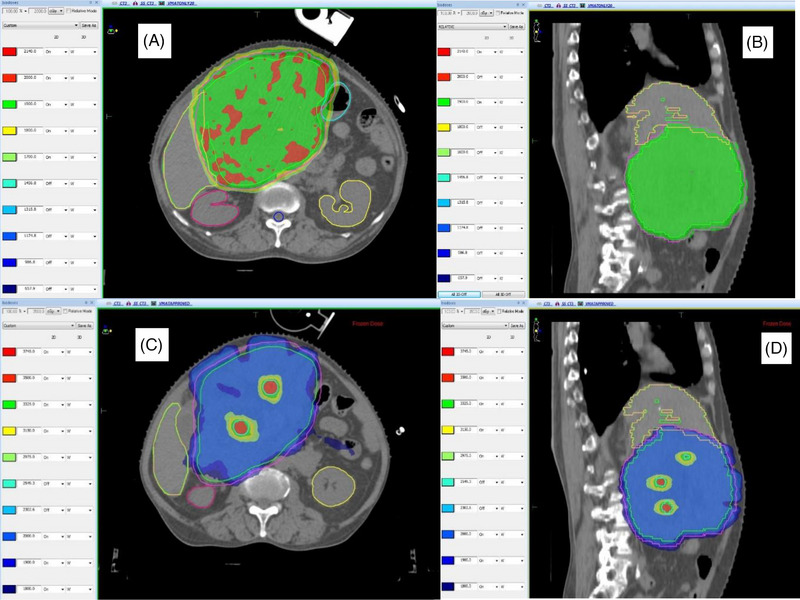

Purpose: Lattice radiotherapy can potentially deliver high doses to the tumor core, while conventional doses to the periphery resulting in improved response rates in large tumors (> 5 cm). We assessed the feasibility of planning lattice radiotherapy and dosimetrically compared it with conventional radiotherapy.

Methods: This retrospective dosimetric study evaluated 10 patients with large tumors (> 5 cm) treated with palliative intent with a dose of 20Gy in five fractions. High-dose lattice points were created at doses of 50Gy in non-hepatic tumors and 35Gy in hepatic tumors. Lattice plans were compared with treatment plans regarding dose coverage and organ-at-risk dosimetry.

Results: Treated sites included soft tissue metastases to the neck, lungs, abdomen, pelvis, and liver. The mean lesion volume was 1103 cc (352-3173 cc). The maximum tumor size was 16 cm. The target volume coverage was > 95% in all but one case (88% to achieve organ constraints). Dosimetry and organ-at-risk doses were similar in both palliative treatment and simulated lattice plans.

Conclusion: Lattice radiotherapy is feasible in large tumors using volumetric-modulated arc therapy and achieves good coverage while meeting organ constraints. However, a prospective clinical evaluation is required to confirm its efficacy.